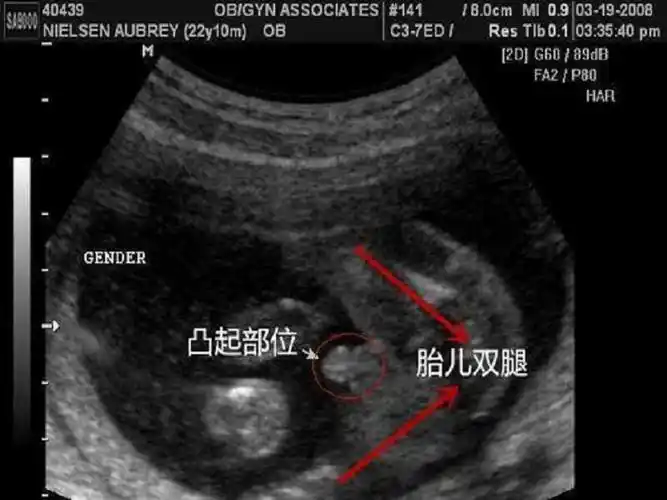

12周nt男宝特点